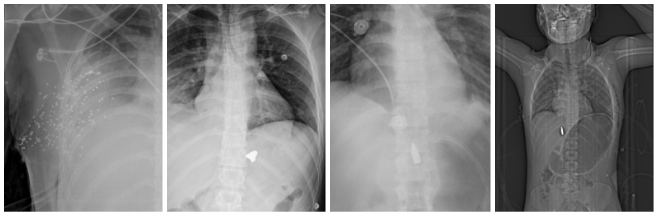

چهار الگوی تیپیک در تصاویر پزشکی: ساچمههای شاتگان در سر و اندام، آسیب پرانرژی در لگن، و گلوله در گردن با جابجایی نای و خطر آسیب عروق بزرگ.

سه مورد پراکندگی متعدد ساچمه شاتگان در صورت، اوربیت و قفسه سینه با خطر نابینایی در کنار یک مورد اصابت پرتابه پرسرعت با نفوذ در جمجمه و آسیب مغزی عمقی

مقایسه الگوهای آسیب تهدیدکننده حیات در قفسه سینه شامل گلوله ۳۹×۷٫۶۲ با پنوموتوراکس و لوله قفسه سینه، اسلاگ ۱۲ گیج با تخریب متمرکز، و شاتگان نزدیکبرد با هموپنوموتوراکس شدید.